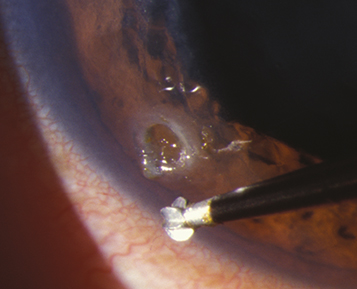

2. Remove the rust ring as completely as possible on the first visit. This may require an ophthalmic burr (See Figure 3.4.2). It is sometimes safer to leave a deep, central rust ring to allow time for the rust to migrate to the corneal surface, at which point it can be removed more easily.

Figure 3.4.2: Burr removal of metallic rust ring.